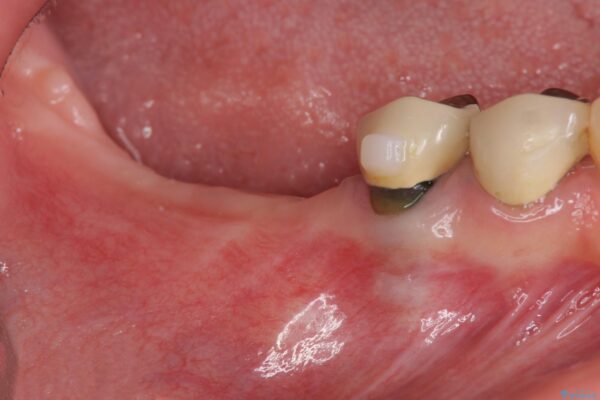

X線写真検査より、クラウンや銀歯の下で歯に大きな虫歯が発生し、抜歯を余儀なくされる状況でした。

虫歯に伴い歯槽骨の吸収も見られたので造骨後、インプラントを用いて咬合機能を回復します。

治療前